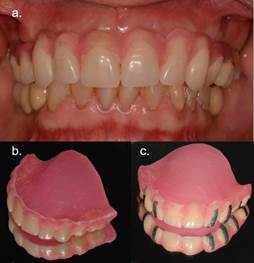

Al instalar la prótesis removible (PR) se pesquisa protrusión labial, línea media superior desviada a la izquierda y un enfilado asimétrico posterior bilateral (Figura 1a, b y c). Debido a esto, se realiza un nuevo enfilado dentario en articulador, sobre una lámina de acrílico de fotocurado para soporte palatino (Profibase®,Voco) y con dientes de acrílico Marché® (Figura 2a y 2b). El enfilado en la zona posterior consta de un premolar y primer molar, para dar contactos posteriores funcionales. Además de corregir parámetros funcionales y estéticos, se confecciona sin flanco para evaluar el soporte labial y perfil facial. Clínicamente se observa una integración facial natural y armónica al agregar exclusivamente dientes (Figura 3).

Posteriormente, este enfilado se transforma en guía radiográfica, agregando marcadores radiopacos en dientes específicos (Figura 2c). Los marcadores radiográficos se confeccionan con bandas de láminas de plomo de 2 mm de ancho y adheridas de vestibular a palatino hasta el límite amelo-cementario. Se solicita un Cone Beam Computarized Tomography (CBCT) con la guía radiográfica y, con el software del CBCT (Romexis®, Planmeca), se realiza el análisis de los sitios y la planificación digital 3D. Se seleccionan implantes Roxolid SLA® Bone Level Tapered (Straumann®), respetando distancias biológicas de Tarnow et al9 y Grunder et al10. Se planifican implantes de 4.8x12mm. para sitios 1.6 y 2.6; de 3.3x14mm. para 1.1 y 1.3; y de 3.3x12mm. para 2.1 y 2.3.